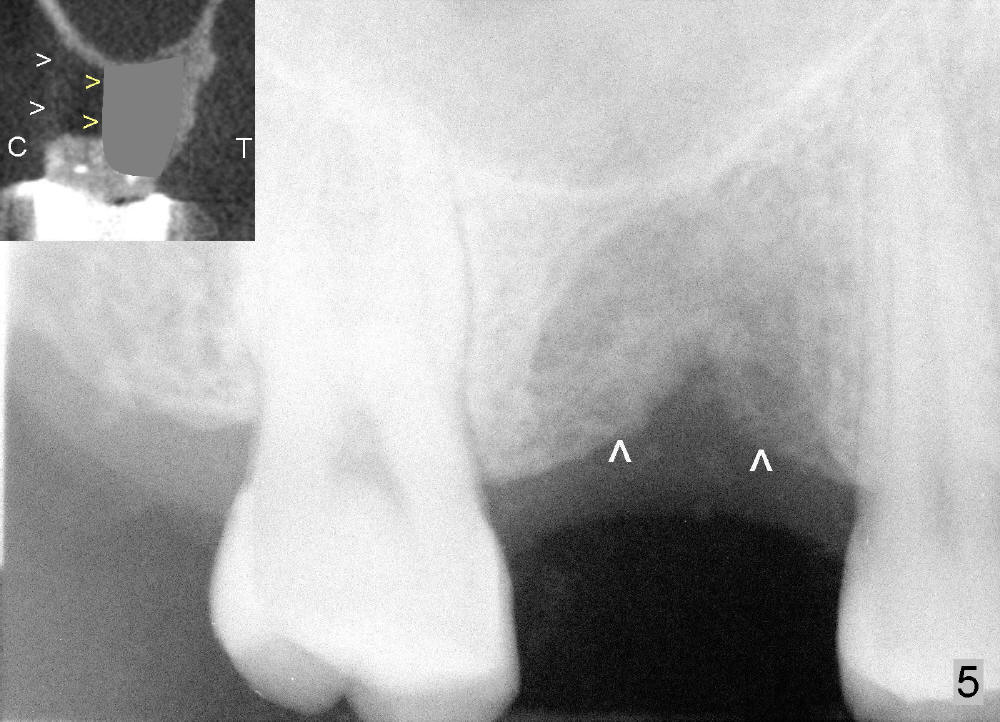

Six months and a half later, the socket appears to be empty (Fig.5) with apparently buccal plate collapse (as indicated by inset in Fig.5). The bony ridge is measured to be ~ 5 mm buccolingually using bone gauge. Osteotomy forms by bone expansion technique. In short, #15 blade is used to split the ridge (slightly lingual), followed by bone scalpels 4,5, and 6 mm, bone blades 4, 5.5 and 7.5 mm, and round tapered osteotomes 2, 3, 4 and 5 mm (Tatum Surgical). The depth is approximately 11 mm. When the last osteotome (4.5 mm round blunt) is used, it deviates too much lingually. A surgical curet is used to explore the osteotomy site. The bony wall appears to be intact except lingual. A 6x11 mm tapered tap is inserted with some resistance (Fig.6). In contrast it is difficult to engage 5.8 mm round tap into the osteotomy site. A 6x11 mm tapered implant is placed with insertion torque 40 Ncm (Fig.7). Amoxicillin is prescribed. The patient is doing fine postop, although the implant is not stable with mild tenderness. Six month post-implantation, the implant appears to have been descended (Fig.8,9, compare to Fig.7).